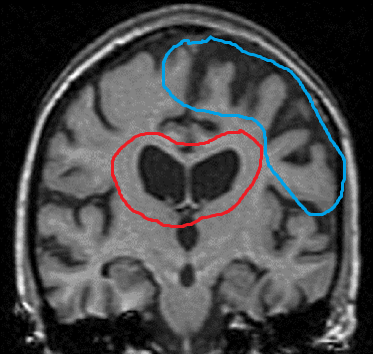

What lobes are effected in Alzheimer’s disease and what are the deficits that usually occur?

What are the abnormalities on the following MRI image? What disease does the patient most likely have?

These findings are common in Alzheimer’s disease patients.